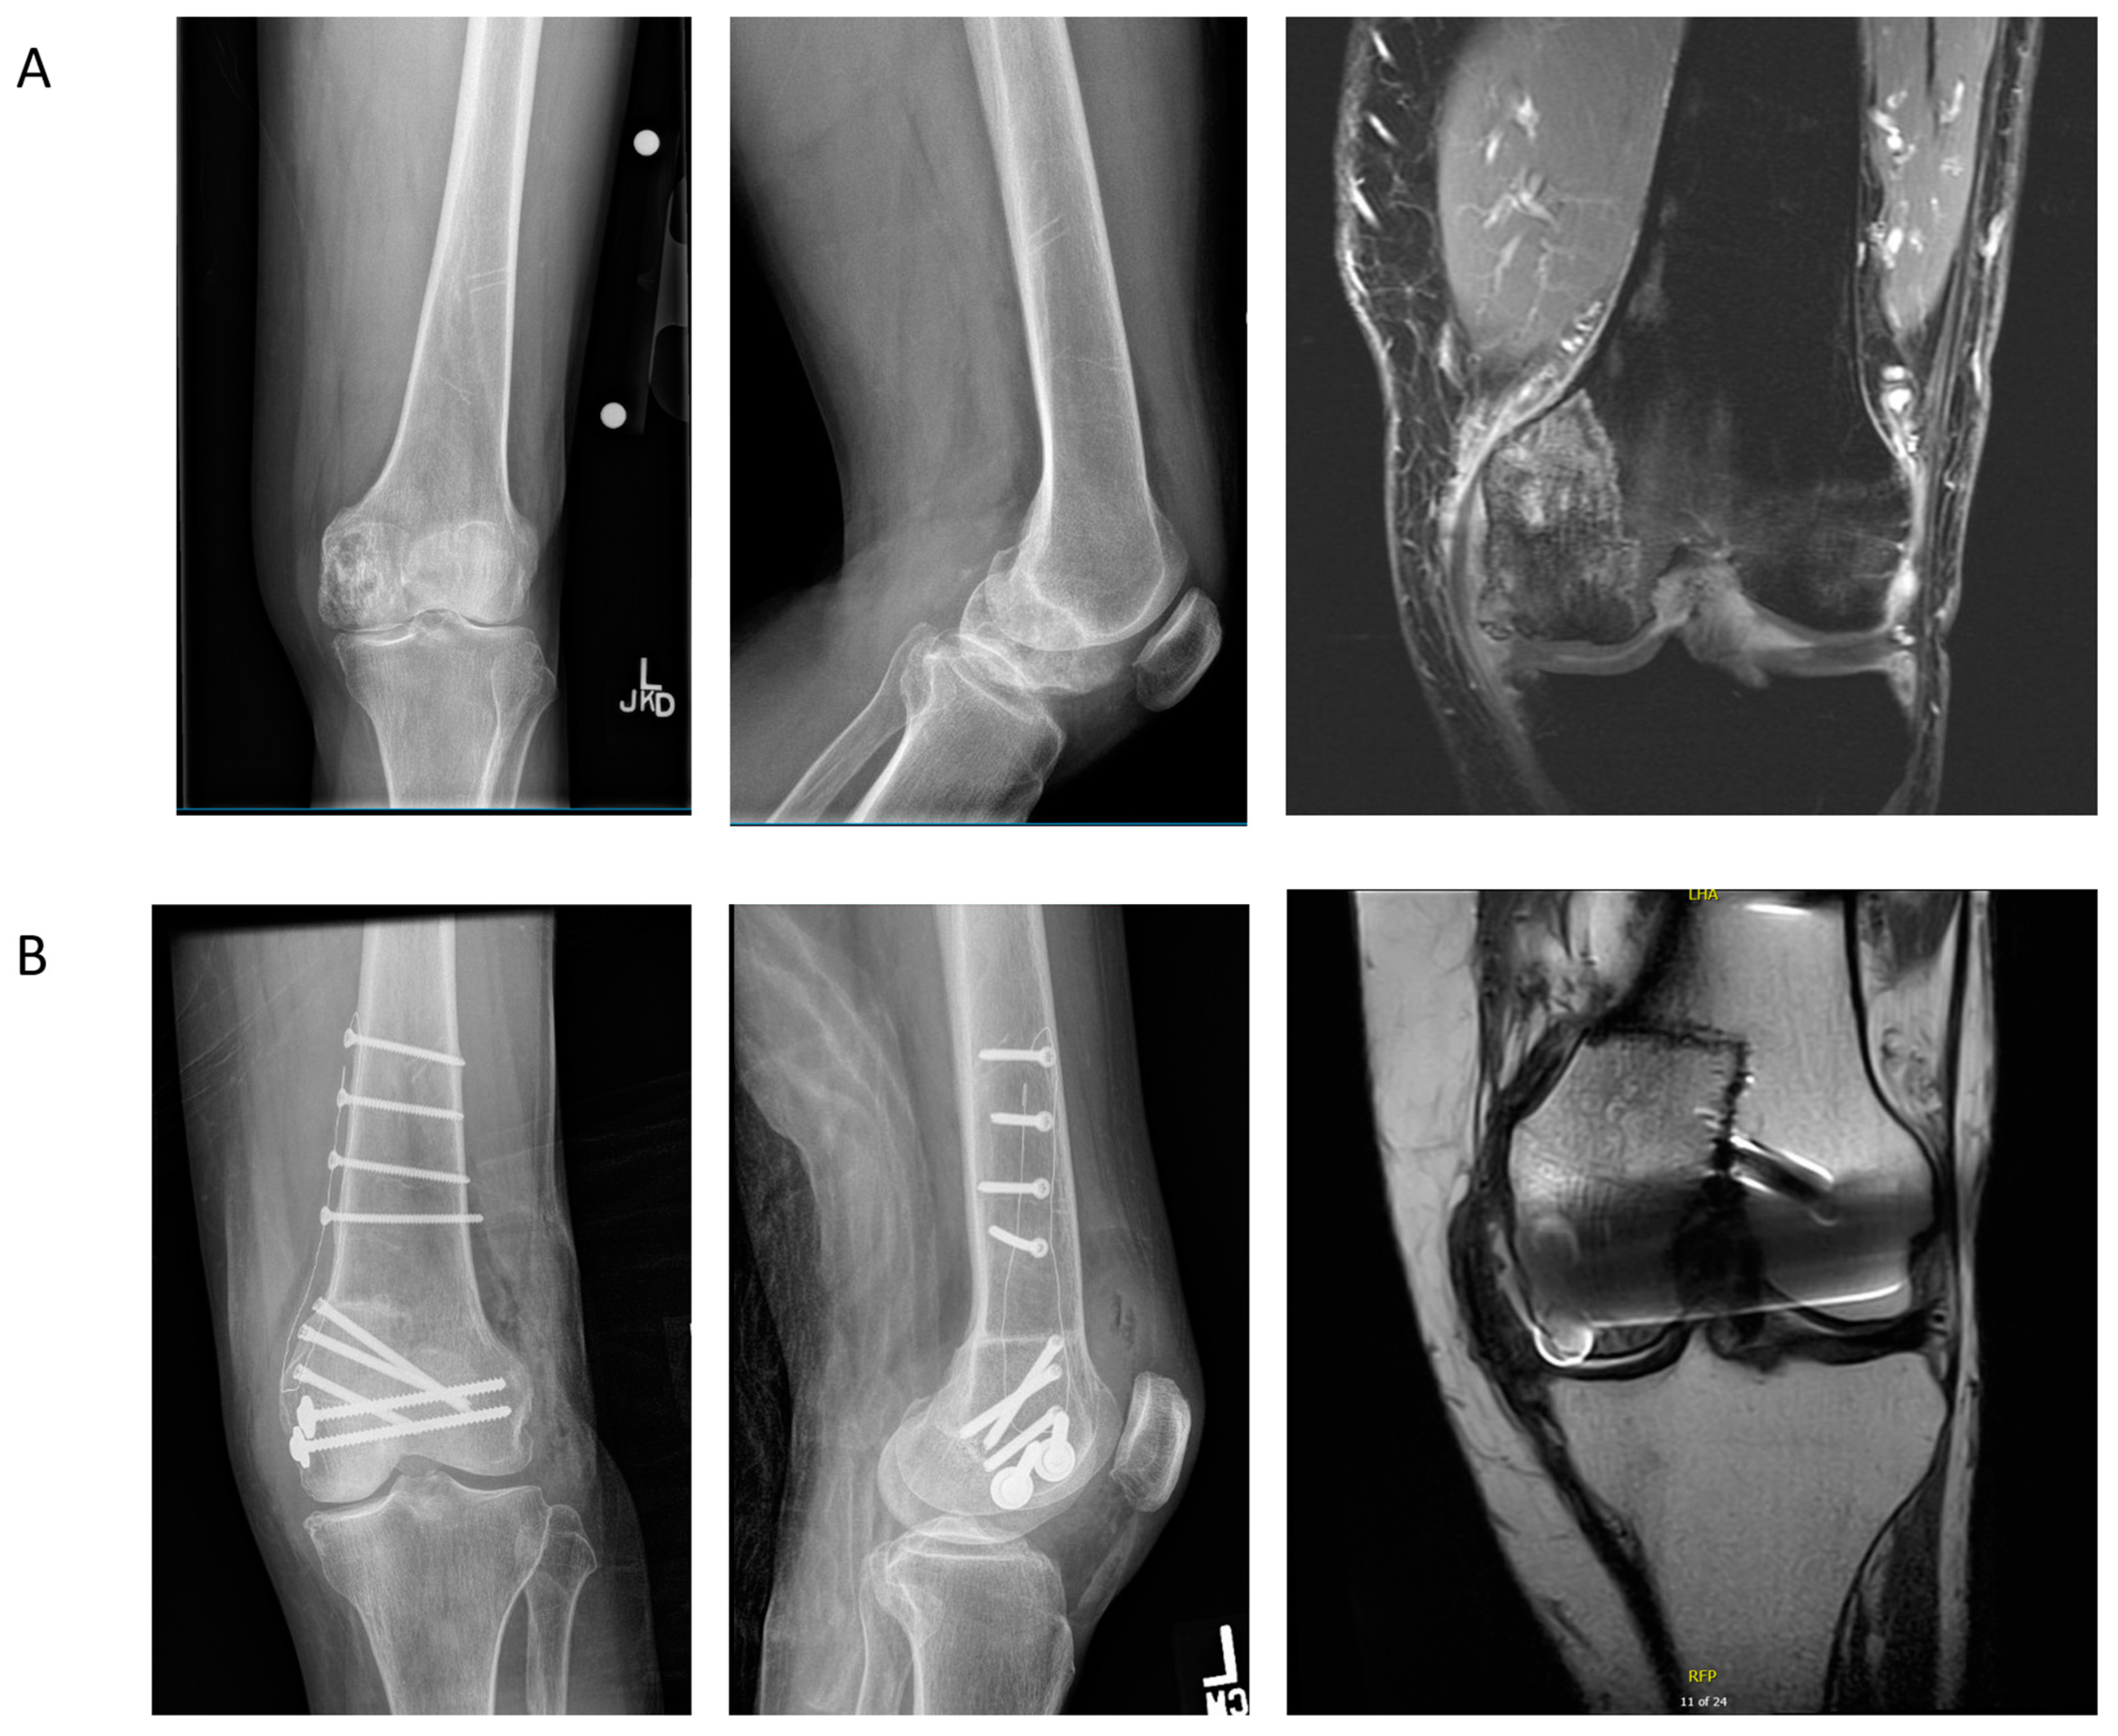

4.3. Case Example 3—Plate and Intramedullary Nail Fixation of Allograft Reconstruction of Femoral Intercalary Resection of Chondrosarcoma

4.4. Case Example 4—Plate Fixation of Allograft Reconstruction of Proximal Humerus following Intercalary Resection of Parosteal Myositis Ossificans

4.5. Case Example 5—Revision Plate and Nail Fixation with Fibular Autograft Augmentation of Prior Tibial Intercalary Allograft Failure